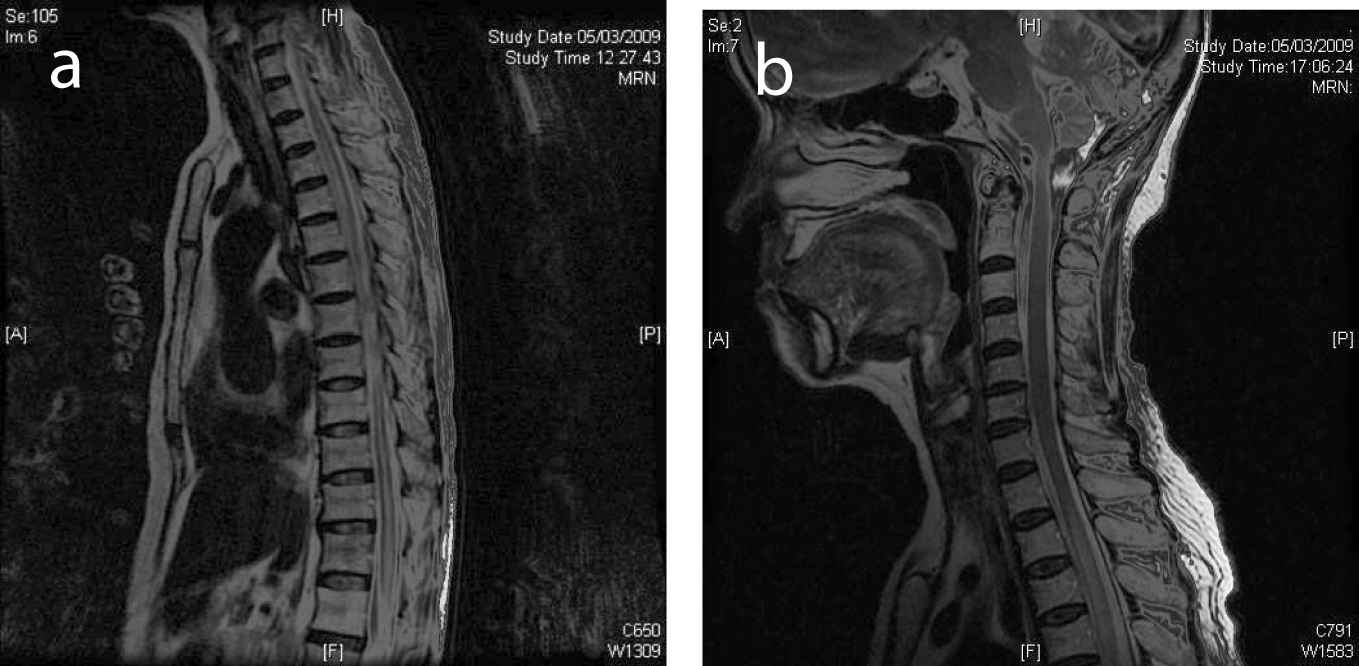

What are the four patterns of lymphoma?

It may exhibit any of the following four patterns: retroocular, anterior preseptal, lacrimal gland involvement, or extension of an adnexal lesion. Lesions that are heterogeneous, with bony destruction, are indicative of high-grade lymphomas, which are usually accompanied by pain. Magnetic resonance imaging.

The information in this article contains billing, coding or other guidelines that complement the Local Coverage Determination (LCD) for Magnetic Resonance Imaging of the Orbit, Face, and/or Neck L34425.